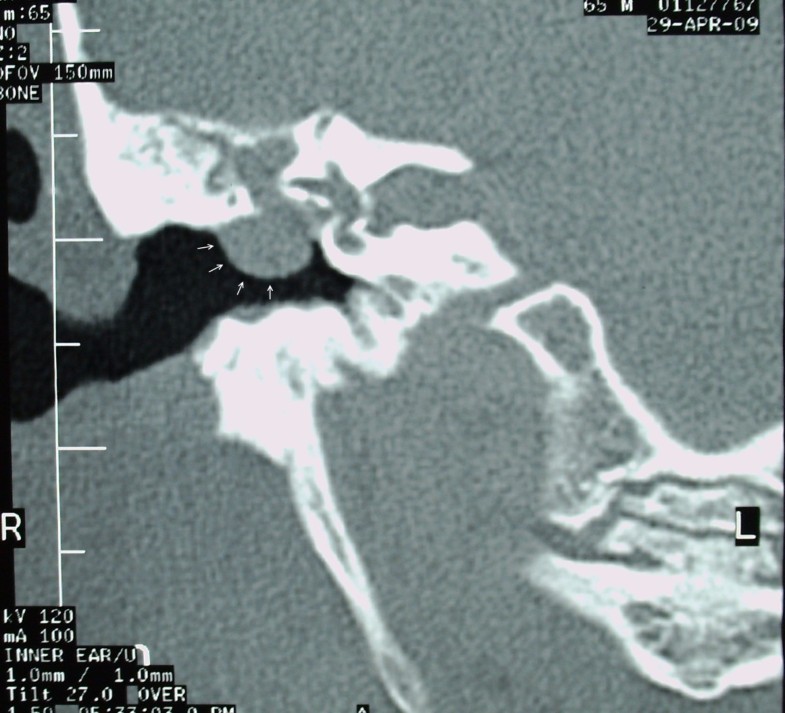

From www.semanticscholar.org

Figure 1 from Clinical Analysis of Cholesterol Granuloma in the Middle Granulomas In Ear They can occur on the. Granulomatosis with polyangiitis (gpa) is an idiopathic vasculitis of medium and small arteries, characterized by necrotizing. Tumors of the ear can be benign or malignant. A granuloma is a cluster of white blood cells and other tissues that are generally not cancerous. An uncommon, benign tumor or cyst located at the petrous apex of the. Granulomas In Ear.